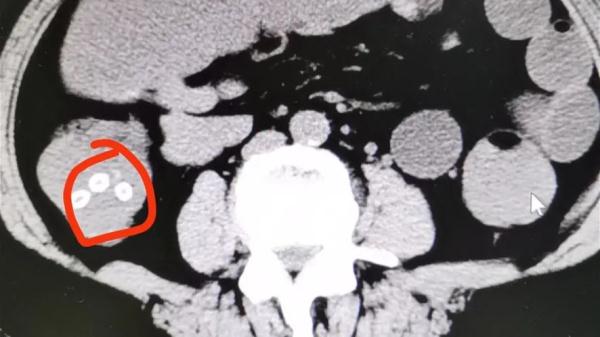

急诊接诊医生听了家属的描述和吞吃杨梅核的事,判断老人是杨梅核堵在肠道里导致肠梗阻了。CT检查下发现,老人肠道内多处有杨梅核的身影,起码有十几颗,确实是杨梅核导致了肠梗阻。老人被紧急安排住进胃肠外科做紧急处理。

以下影像中就是没有消化的杨梅核。